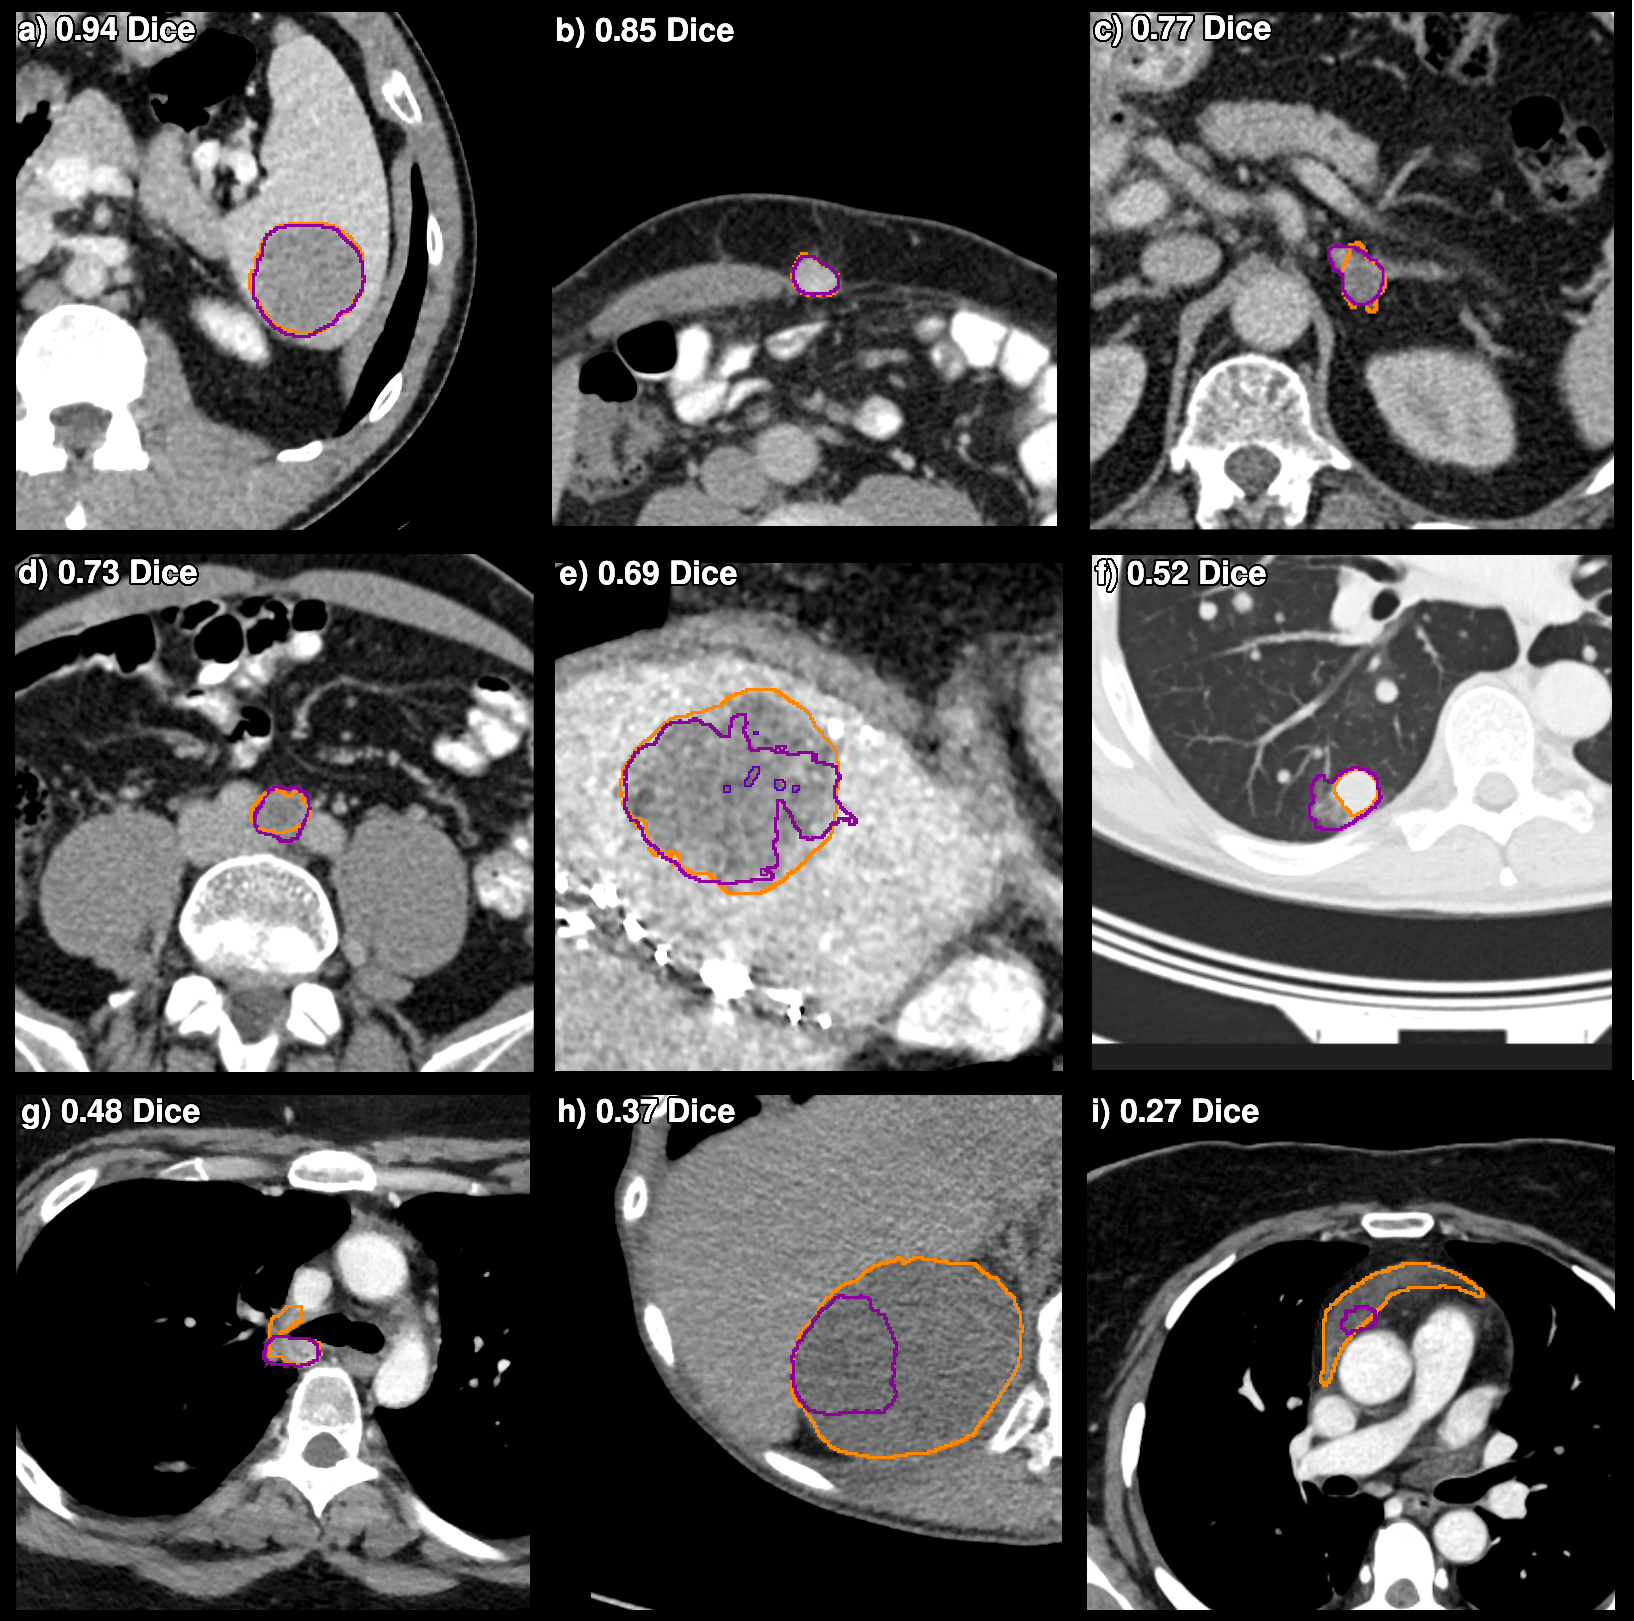

The results presented in Table 2, demonstrate considerable variations in segmentation performance across different lesion types, a finding consistent with outcomes from previous segmentation challenges [Antonelli et al., 2022, Bilic et al., 2023, Heller et al., 2023, Pedrosa et al., 2021]. Lesions in the colon or pancreas are particularly challenging to segment due to their low contrast with surrounding healthy tissue and their irregular shapes. Figure 6 illustrates the variation in model performance across nine test cases. Lesion hh and i𝑖i highlight the issue of under-segmentation of larger lesions, which is a consistent weakness of the evaluated models. One possible explanation is that larger lesions appear less frequently in the training data (see Figure 1). Future work could try to address this problem by over-sampling large lesions during training. Lesion f𝑓f is an example of the inherent subjectivity of certain lesion boundaries, with the radiologist only segmenting the solid component of the lung lesion and the algorithm including the ground-glass area. Similar subjectivity can also be observed in merging liver lesions or lymph nodes. Future iterations of the challenge should explore how to minimize this subjectivity.

Refer to caption

Figure 6: Ground truth (orange line \blacksquare) and baseline model prediction (purple line \blacksquare) on axial slices from the test set. The 3D Dice score for each lesion is included in the top-left corner. The lesions visualized are: a) spleen lesion b) lesion in the abdominal wall c) adrenal lesion d) abdominal lymph node e) liver lesion f) lung lesion g) mediastinal lymph node h) kidney lesion i) Pericardial lesion. Lung lesions are visualized using Window Level: -500 HU, Window Width: 1400 HU. Lesions outside the lungs with WL: 350 WW: 40.